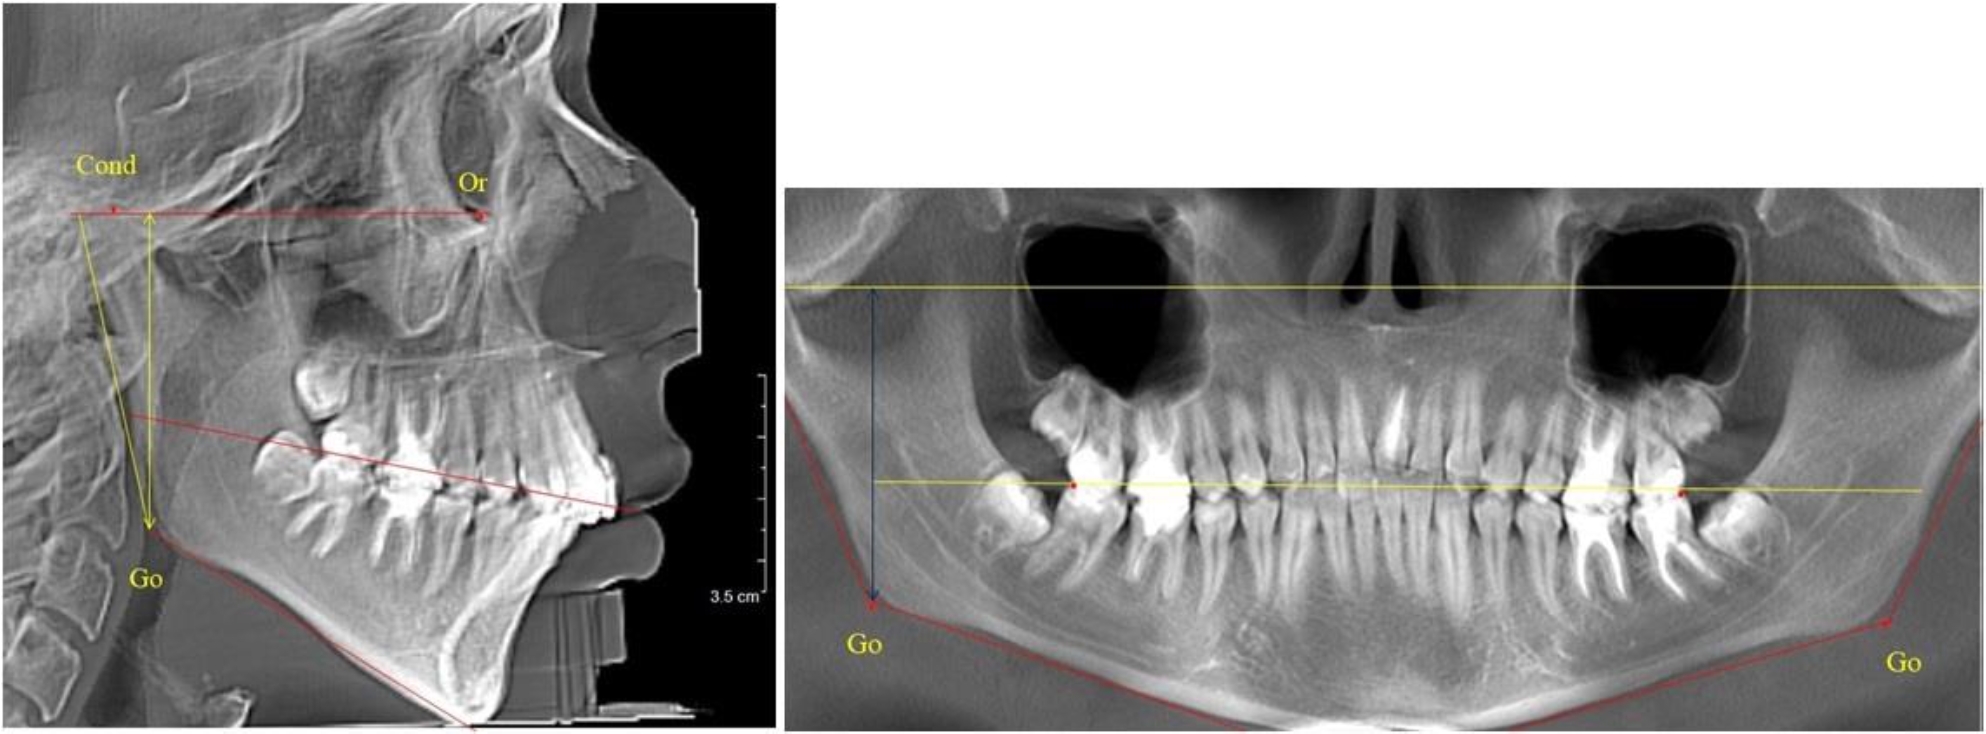

В 1-й группе были проанализированы 7 телерентгенограмм и 7 ортопантомограмм, что составило (6,60 ± 2,41) % от числа изученных рентгенограмм. На всех парах рентгенограмм угол нижней челюсти, измеренный на телерентгенограмме, соответствовал углу, полученному при построении угла на ортопантомограмме. Окклюзионная линия практически однотипно делила ветвь на два отдела (рис. 1).

Как на ортопантомограмме, так и на телерентгенограмме высота ветви у детей в периоде сформированного прикуса молочных зубов составляла (42,21 ± 2,48) мм. При этом высота верхней окклюзионно-суставной части была (22,57 ± 1,46) мм, а нижней – (19,64 ± 1,54) мм.

Учитывая вариабельность абсолютных величин, определи относительные показатели соразмерности частей ветви нижней челюсти. Так, отношение высоты верхней части ветви к нижней в среднем составляло 1,15 ± 0,13. Отношение общей высоты ветви к верхней ее части составляло 1,87 ± 0,14, а отношение общей высоты ветви к нижней ее части было 2,14 ± 0,16 и достоверных различий по относительному показателю отношения всей высоты к верхней и нижней челюсти нами не отмечено (р ˃ 0,05). При этом визуально обе части выглядели примерно равноразмерными.

Рис. 1. ТРГ и ОПТГ пациента 1-й группы